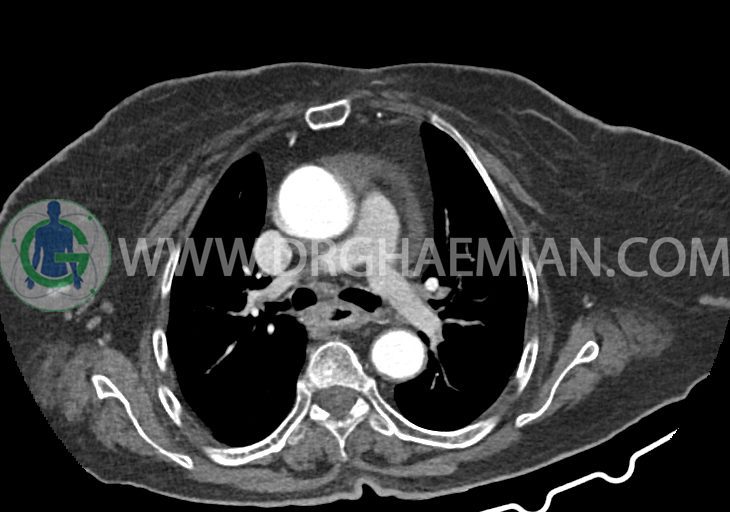

در سی تی اسکن اسپیرال ریه و مدیاستن – شکم و لگن با و بدون کنتراست خوراکی و وریدی (مولتی دیدکتور 16 با مقاطع ظریف و بازسازی های ساژیتال و کرونال):

–دیلاتاسیون نیمه فوقانی مری توراسیک ناشی از افزایش ضخامت circumferential توده مانند در یک سوم دیستال مری به طول 50mm ، که می تواند مطرح کننده انفیلتراسیون تومورال همراه با تنگی

تراشه و برونش های اصلی نرمال اند. پنومونی، پلورال افیوژن، جابجایی محتویات مدیاستن ، فیبروز ریوی و Collection مشهود نیست.